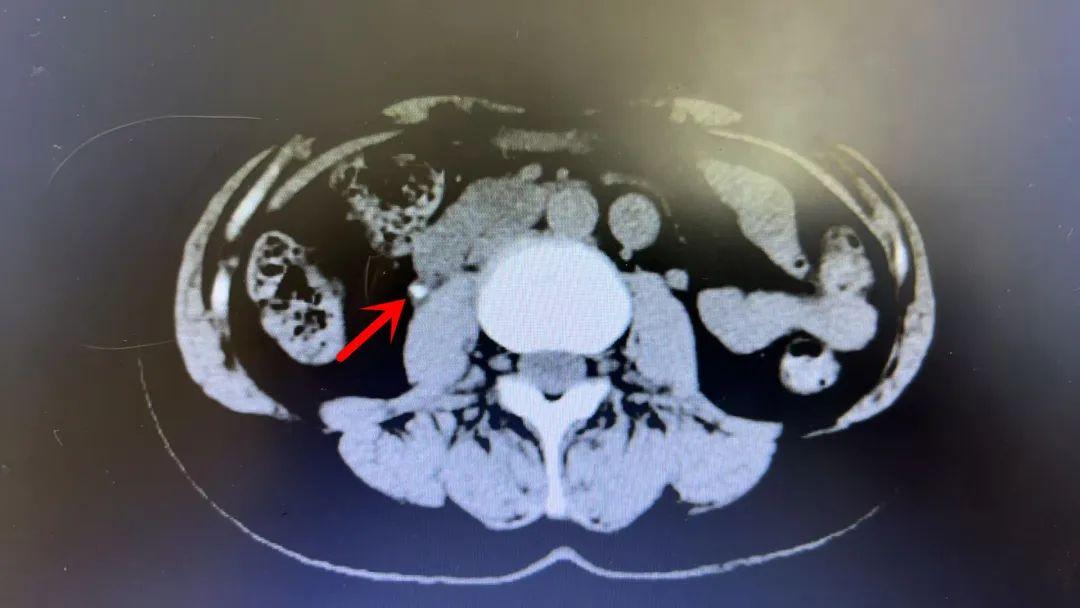

CT显示下的结石。

急诊医生马上为小张安排了CT检查,结果显示一颗直径约5毫米的结石卡在了他的右侧输尿管中段,正是引发这场“肾绞痛”的罪魁祸首。